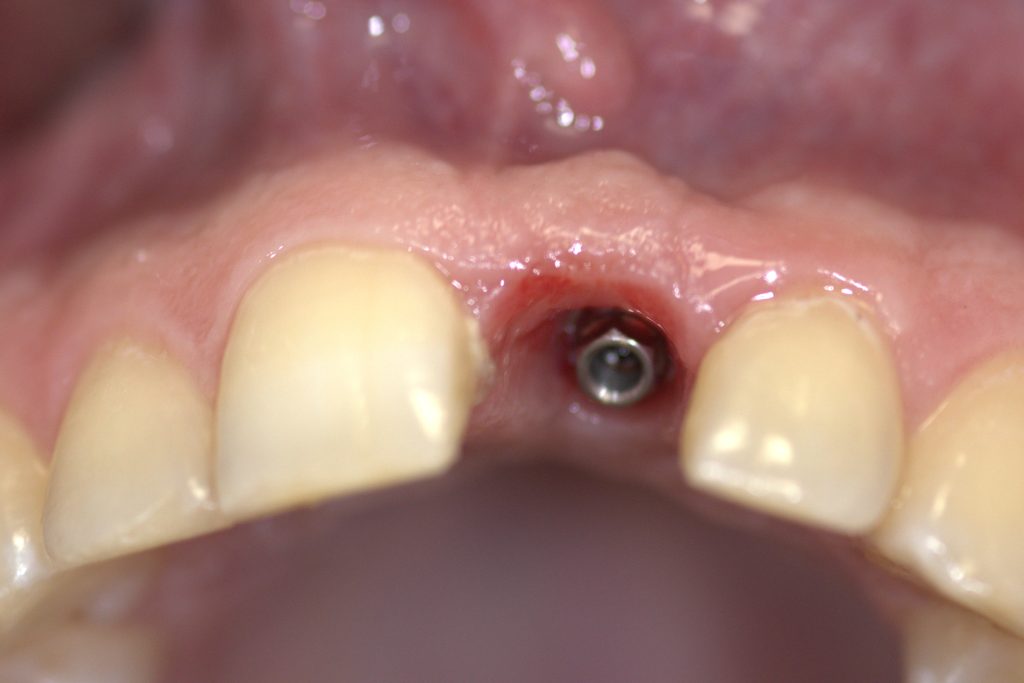

Post operative state – immediate loading